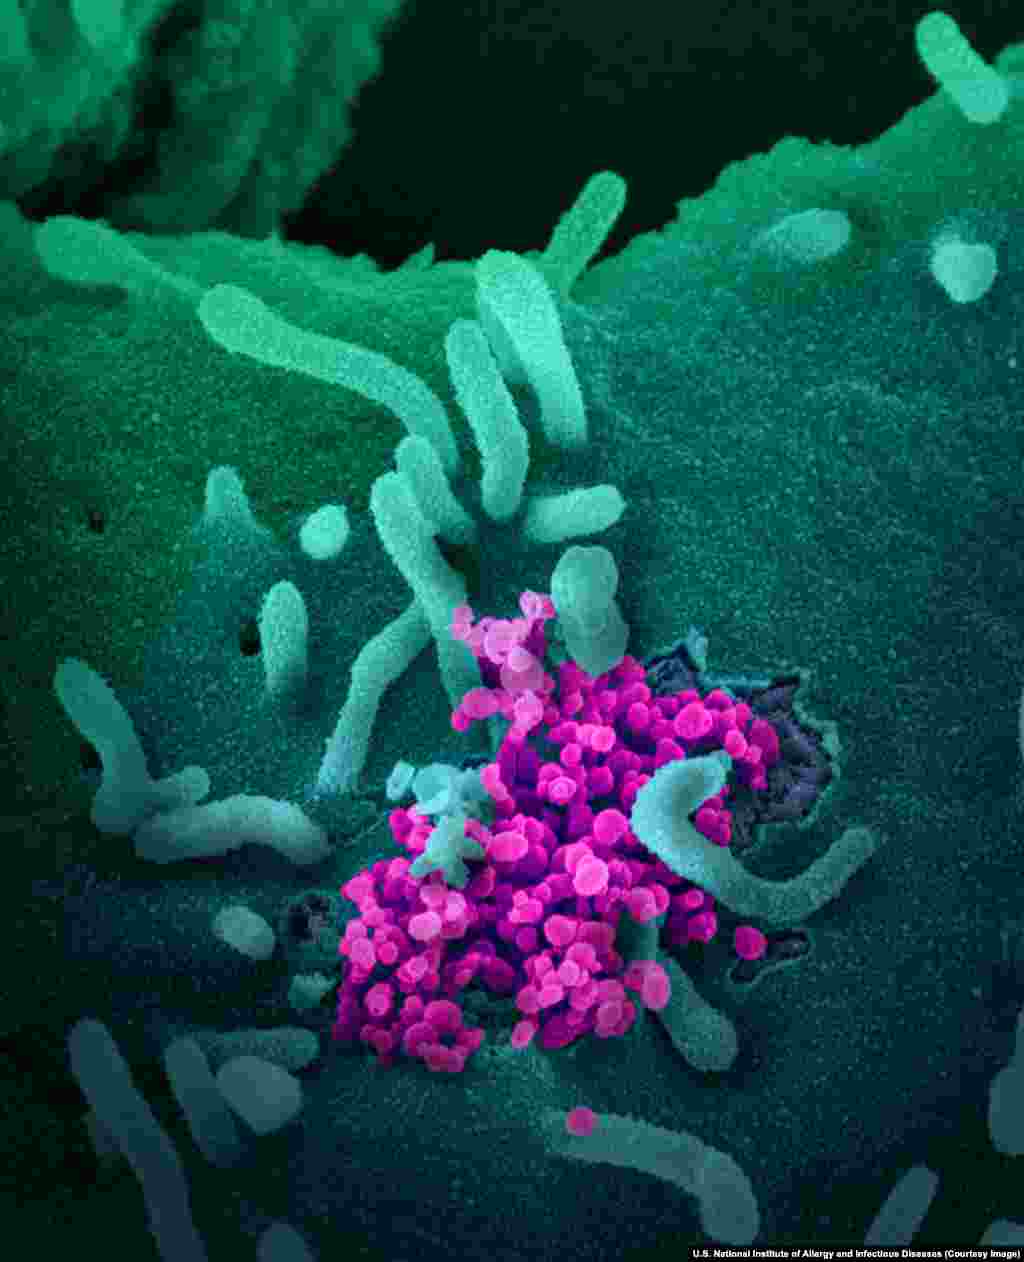

2

Вирионы SARS-CoV-2, разрастающиеся в клетке человеческого организма.

Все фотографии в этой галерее раскрашены с использованием специальных программ, включая Photoshop.

Все фотографии в этой галерее раскрашены с использованием специальных программ, включая Photoshop.